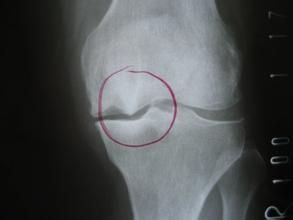

X線檢查

骨刺X線平片不僅為骨質增生的常規檢查方法,有的學者還認為骨質增生的X線檢查是追蹤病情變化的金標準。

骨刺的X線片可分為五級:

0級:無改變;

1級:輕微骨贅;

2級:明顯骨贅,關節間隙正常;

3級:骨贅外關節間隙中度狹窄;

4級:骨贅外關節間隙嚴重狹窄,伴軟骨下骨硬化。

拍膝關節片時,病人應取站立位拍前後位和側位片,髖關節和手關節可只拍前後位片。在早期階段,X線片大多正常,中晚期可見關節間隙不對稱性狹窄、關節面下骨硬化和變形、關節邊緣骨贅形成,關節面下囊腫和關節腔游離液體等。

骨質增生的x線特點為:關節面硬化變形;關節鼠;關節邊緣骨贅;關節間隙狹窄,如在膝關節,可小於3毫米;軟骨下囊性變,其邊緣分界清楚;骨變形或關節半脫位。